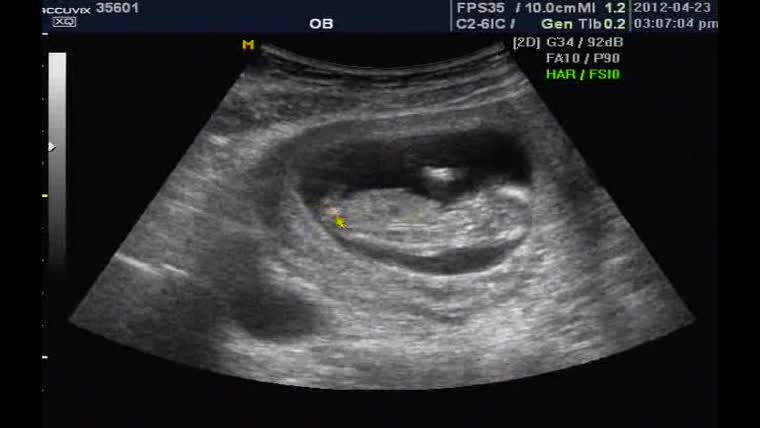

출산 날짜: 2012년 11월 09일

출산 시간: 오전 11시 56분

아기 체중: 4.16kg

아기 성별: 남

그야말로 핫 한 사진이네요^^

태어난지 3일도 채 되지않은 따끈 따끈한 신생아적 사진.